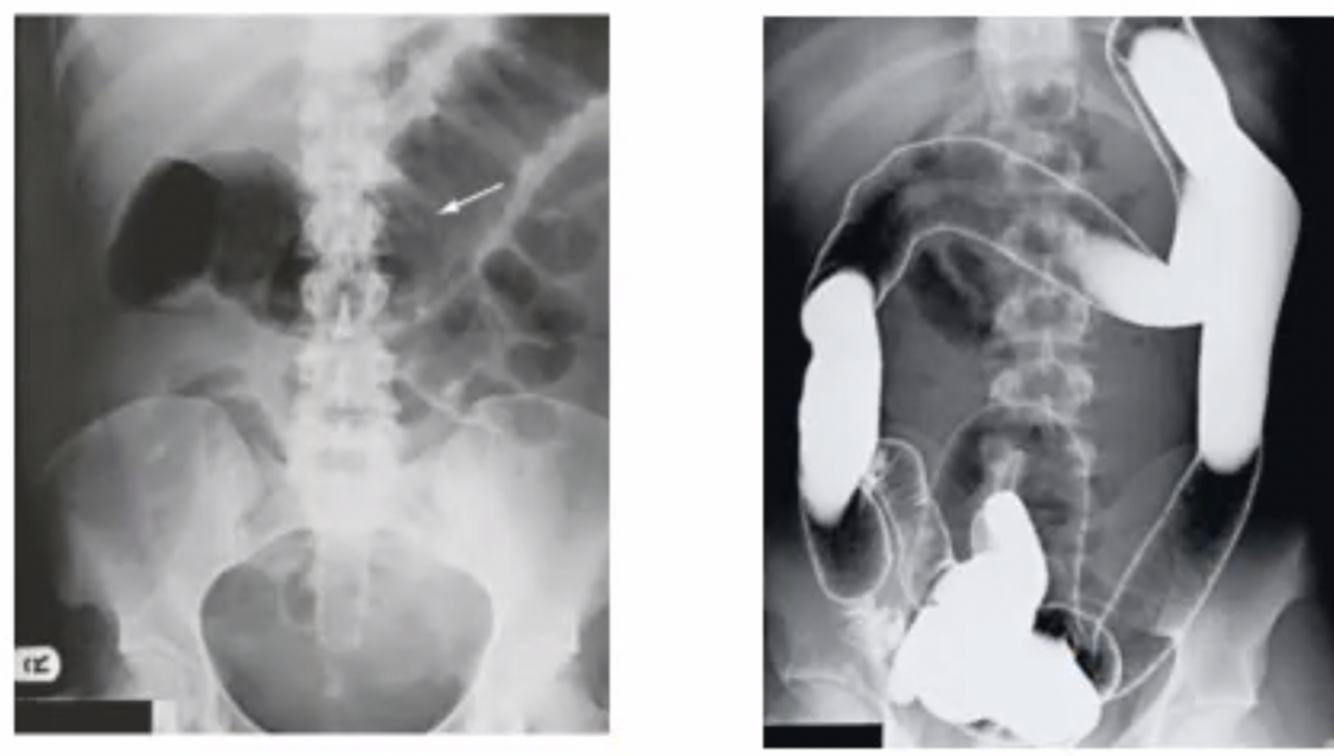

metodos de imagen para dx de cuci

A

-rx

-TC con contraste (engrosamiento del colon, perdida de haustras)

-enema de bario